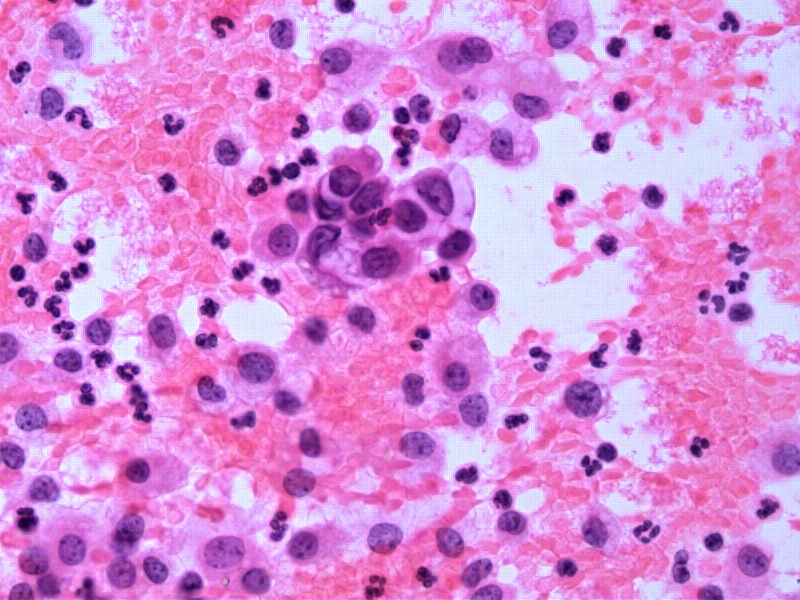

B11:胸水腺癌

B12:胸水腺癌

B13:胸水腺癌